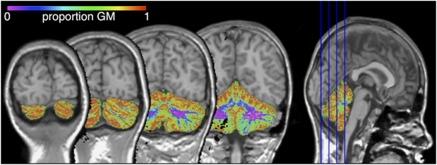

All brain scans were coded to ensure rater blindness to subject identity and diagnosis. The T1 images were automatically placed in Talairach orientation40 without scaling, by registering them to a model brain in Talairach orientation.41 After linear registration to the T1-weighted image, the intracranial segment served as a mask for all further segmentation steps. The T1-weighted images were corrected for field inhomogeneities using the N3 algorithm.42 An automatic image-processing pipeline was used to define the volume of total brain, cerebral and cerebellum volume, and gray matter (GM) and white matter (WM). The software used included updated versions of previously described histogram analysis, mathematical morphology operations and anatomical knowledge based rules to connect all voxels of interest.43, 44 The gray/white separation algorithm takes into account the effects of partial voluming by calculating the proportion of GM, WM and cerebrospinal fluid for each voxel.45 Figure 1 shows a typical GM probability map for cerebellum. Segments for cerebrum and cerebellum were visually checked and edited to ensure an accurate segmentation. Suboptimal scan quality precluded gray/white separation for 4 of 45 children in the analyses for cigarette exposure in ADHD, for 1 of 33 children in the analyses on alcohol exposure in ADHD and for 1 of 28 children in the analyses on control subjects exposed to alcohol.

Figure 1.

A typical gray/white probability map in cerebellum for a subject in this study. GM, gray matter.